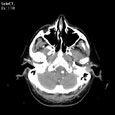

Фузиформная аневризма основной артерии. Фузиформная аневризма основной артерии

Пациент K., 49 лет

Фузиформная аневризма основной артерии.

ЦКБ5 Южной железной дороги, отделение лучевой диагностики.

На КТ-сканах головного мозга в условиях ангиографии (в/в ультравист 300 - 100,0) контрастированы сосуды вилизиевого круга. Определяется расширение основной артерии до 11 мм на протяжении 26 мм с изгибом на этом уровне по типу кинкинг. Проксимальнее участка расширения на протяжении 12 мм до уровня бифуркации основной артерии определяется ее дугообразное искривление за счет давления со стороны объемного образования, располагающегося ретро-супраселлярно по средней линии и огибающего (либо исходящего из) спинки турецкого седла размерами 20х14 мм.

Оральные отделы ствола и ножки мозга оттеснены кверху.

Сильвиев водопровод сдавлен в оральных отделах.

В паренхиматозной фазе увеличение плотности образования не более чем на 10-15 HU.

Расширение 3-го и боковых желудочков.

Конвекситальные подпаутинные пространства не дифференцируются (поддавлены).

Фузиформная аневризма основной артерии. Внемозговой объемный процесс основания, возможно исходящий из блюменбахова ската (менингиома?). Окклюзионная гидроцефалия. Окклюзия ликворных путей на уровне оральных отделов сильвиева водопровода.